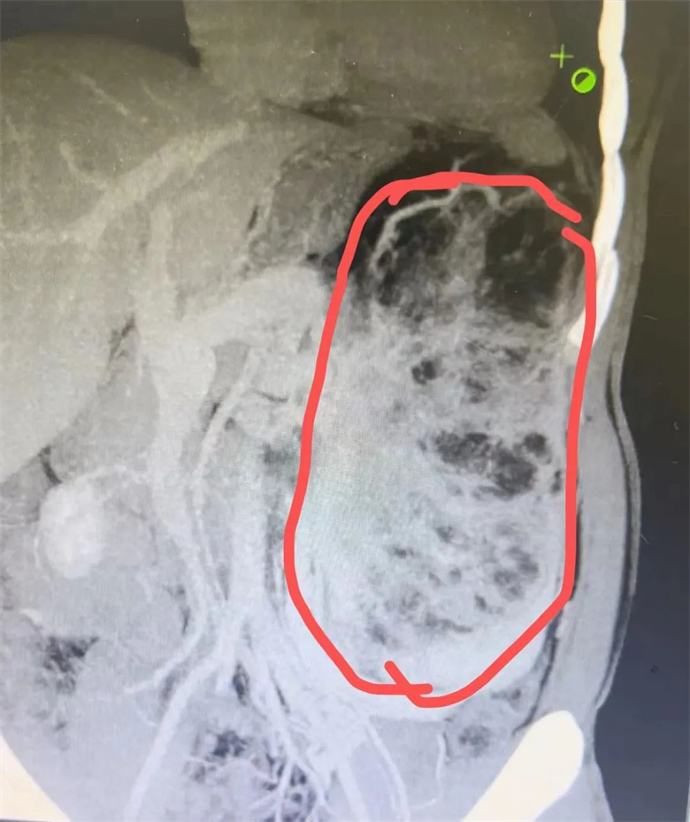

近日,我院泌尿外科會診一位四十多歲男性患者時發(fā)現(xiàn),該患者腹部有一巨大腫瘤,直徑近30cm,已將該患者胃、胰腺、脾臟及部分腸管擠壓移位,且腫瘤內(nèi)可見大量動靜脈畸形,存在極大的出血風險,一旦出血將危及患者生命,客觀告知患者及家屬相關病情后,患者及家屬憂心忡忡,基本的日?;顒佣夹挠形窇?,充分溝通后,轉(zhuǎn)入泌尿外科,擬行手術治療。

轉(zhuǎn)入泌尿外科后,強永春主任及專家組積極術前準備,仔細閱片,充分討論,明確此腫瘤來源為左側(cè)腎臟,多考慮為腎臟血管平滑肌脂肪瘤,俗稱“錯構瘤”。周莉護士長帶領護理組通過傾聽、解釋、鼓勵、提供支持、建立信任等來安撫患者的憂心忡忡,幫助他們更好地應對疾病??茖W、客觀的指導患者的術后康復。

錯構瘤屬于良性腫瘤,絕大多數(shù)錯構瘤患者沒有明顯的癥狀,一些比較大的錯構瘤,可能會出現(xiàn)局部壓迫癥狀或壓迫周圍臟器,出現(xiàn)相應的癥狀。腎錯構瘤最大的危害在于,體積較大的錯構瘤突然破裂時,患者會出現(xiàn)腰腹疼痛和血尿等癥狀,嚴重的大出血患者可以在腹部觸及到包塊,甚至有休克癥狀。因此當腫瘤直徑大于4cm時,一般會積極建議手術,減少自發(fā)破裂的風險。但該患者平素未行體檢,腫瘤已近30cm,因此貿(mào)然手術處理存在巨大的風險。

強永春主任帶領泌尿外科團隊積極協(xié)調(diào),提前預約腫瘤介入王忠主任,于術前行介入栓塞,減少術中出血風險;同時聯(lián)系輸血科提前術中備血;因腫瘤已侵及腎臟大部及腎臟血管,無法保留腎單位行腎部分切除,故先側(cè)臥位行后腹腔鏡下微創(chuàng)手術,游離并處理腎臟血管,確保切除時安全,再仰臥位行錯構瘤及腎臟切除;充分準備后,手術按預定方案如期進行,歷時6小時,成功拆除“定時炸彈”。目前患者已出院恢復了日常工作。